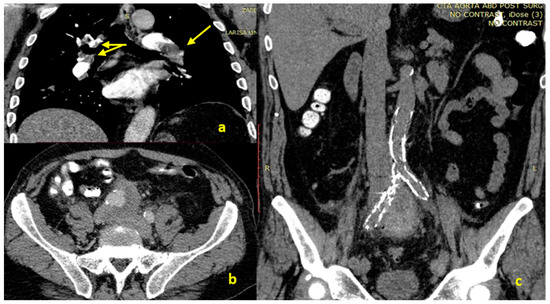

Bilateral Deep Vein Thrombosis and Pulmonary Embolism Due to Right Common Iliac Artery Aneurysm with a Contained Rupture

2. Case Presentation